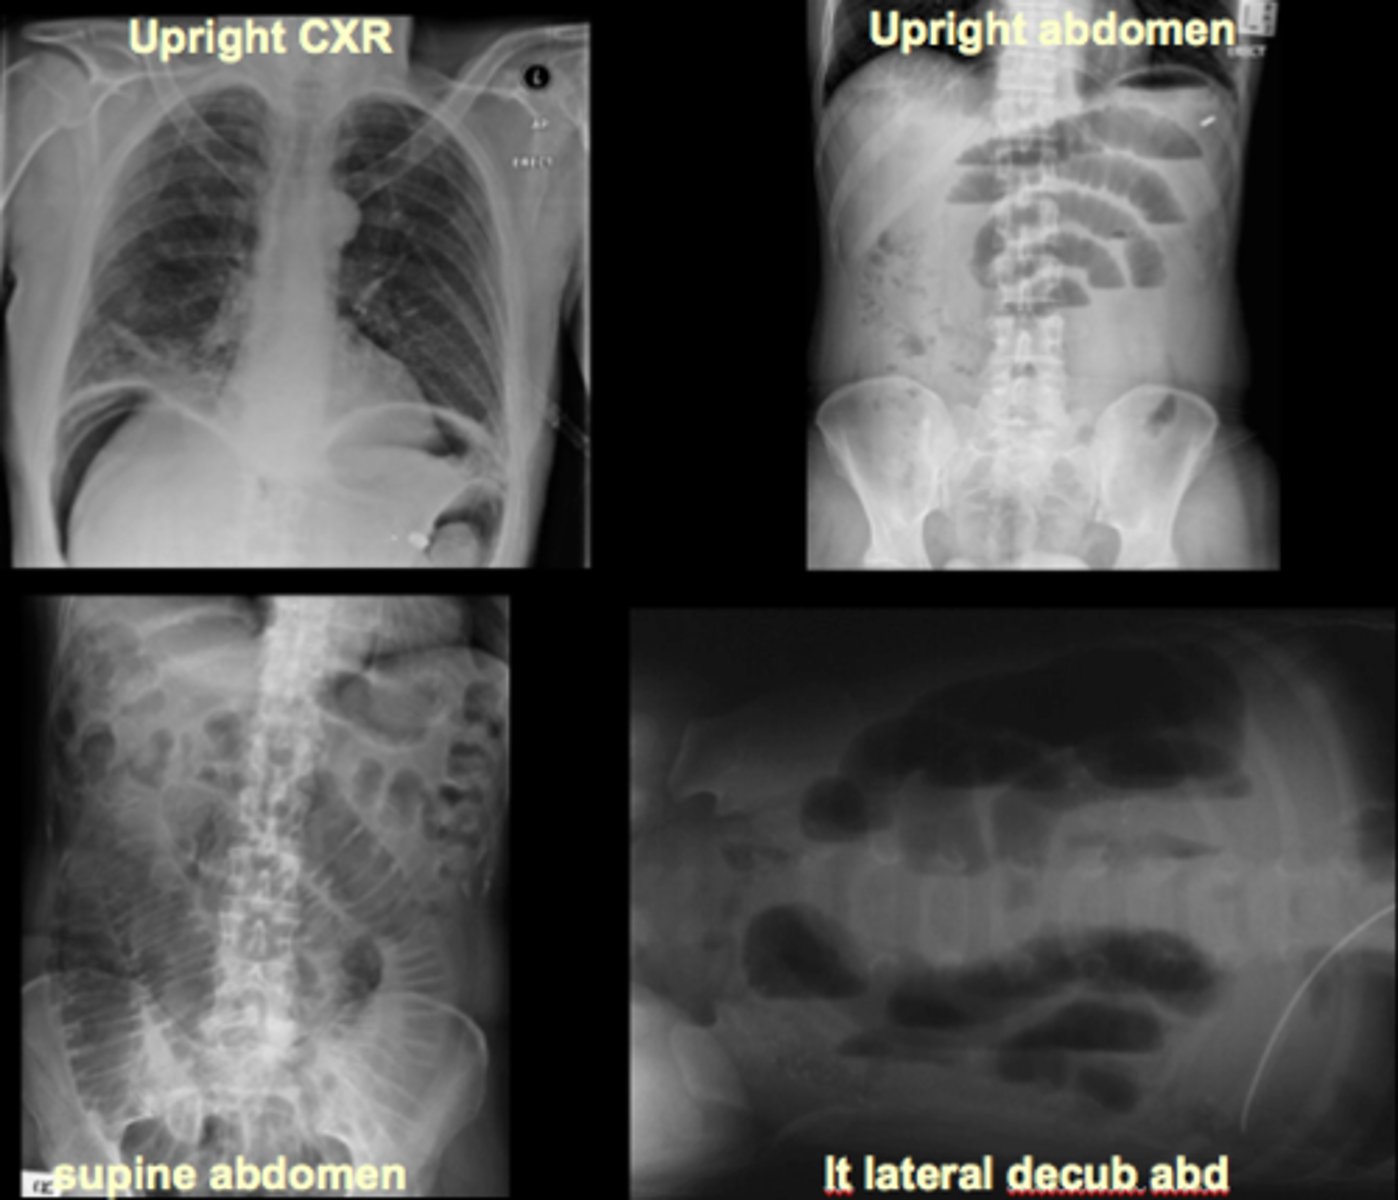

acute abdominal series

supine abdomen/KUB/scout - bowel gas pattern, calcifications, masses

upright abdomen - free air, air-fluid levels

upright chest - free air, pneumonia, pleural effusions